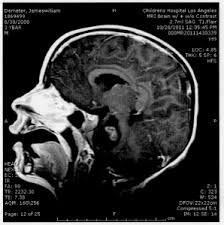

Pediatric Brain Tumors Symptoms And Causes Mayo Clinic from www.mayoclinic.org Double vision or not being able to close the eyelids. The exact causes of cancer are still unknown. It usually causes no symptoms. Astrocytomas are tumors that start in certain brain cells called astrocytes, which are a type of glial cell. Worldwide, cancer has become so prevalent and devastating that some may use the phrase like curing cancer when describing something unfeasible or highly complicated. While glandular fever can be very unpleasant, it usually passes within a few weeks and it doesn't mean that you go on to develop cancer. Tests that examine the brain and spinal cord are used to detect (find) childhood brain and spinal cord tumors. Promising findings are emerging from a study coordinated by a research team of the university of trento on medulloblastoma, the most common malignant brain tumor in children affecting the central.